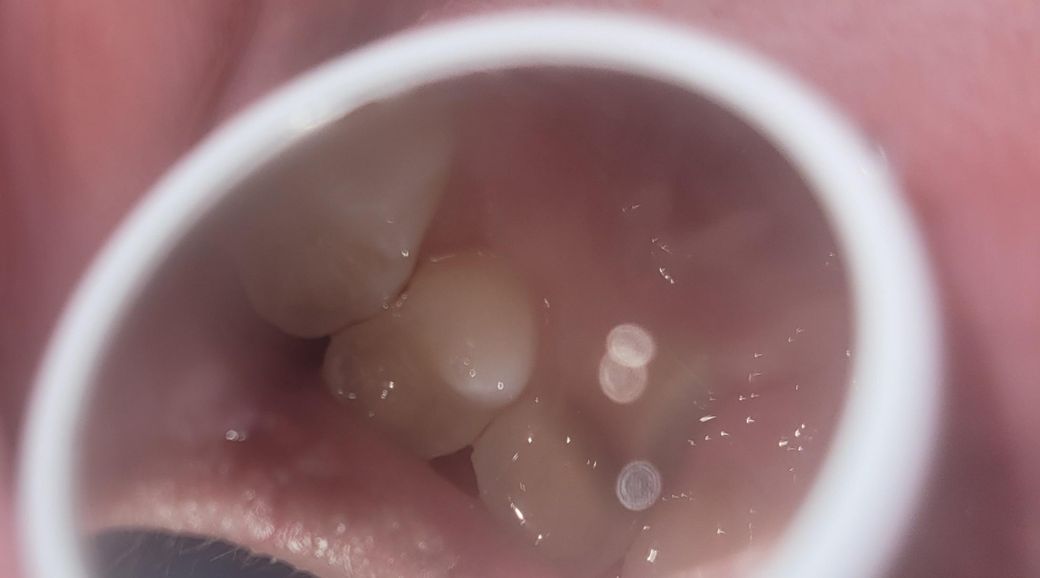

소구치와 대구치 사이가 까맣게 보여요.충치일까요?

제가 양치하고 치아를 살펴보니 소구치와 대구치 사이가 까맣게 보였습니다.

• 1번 째 사진